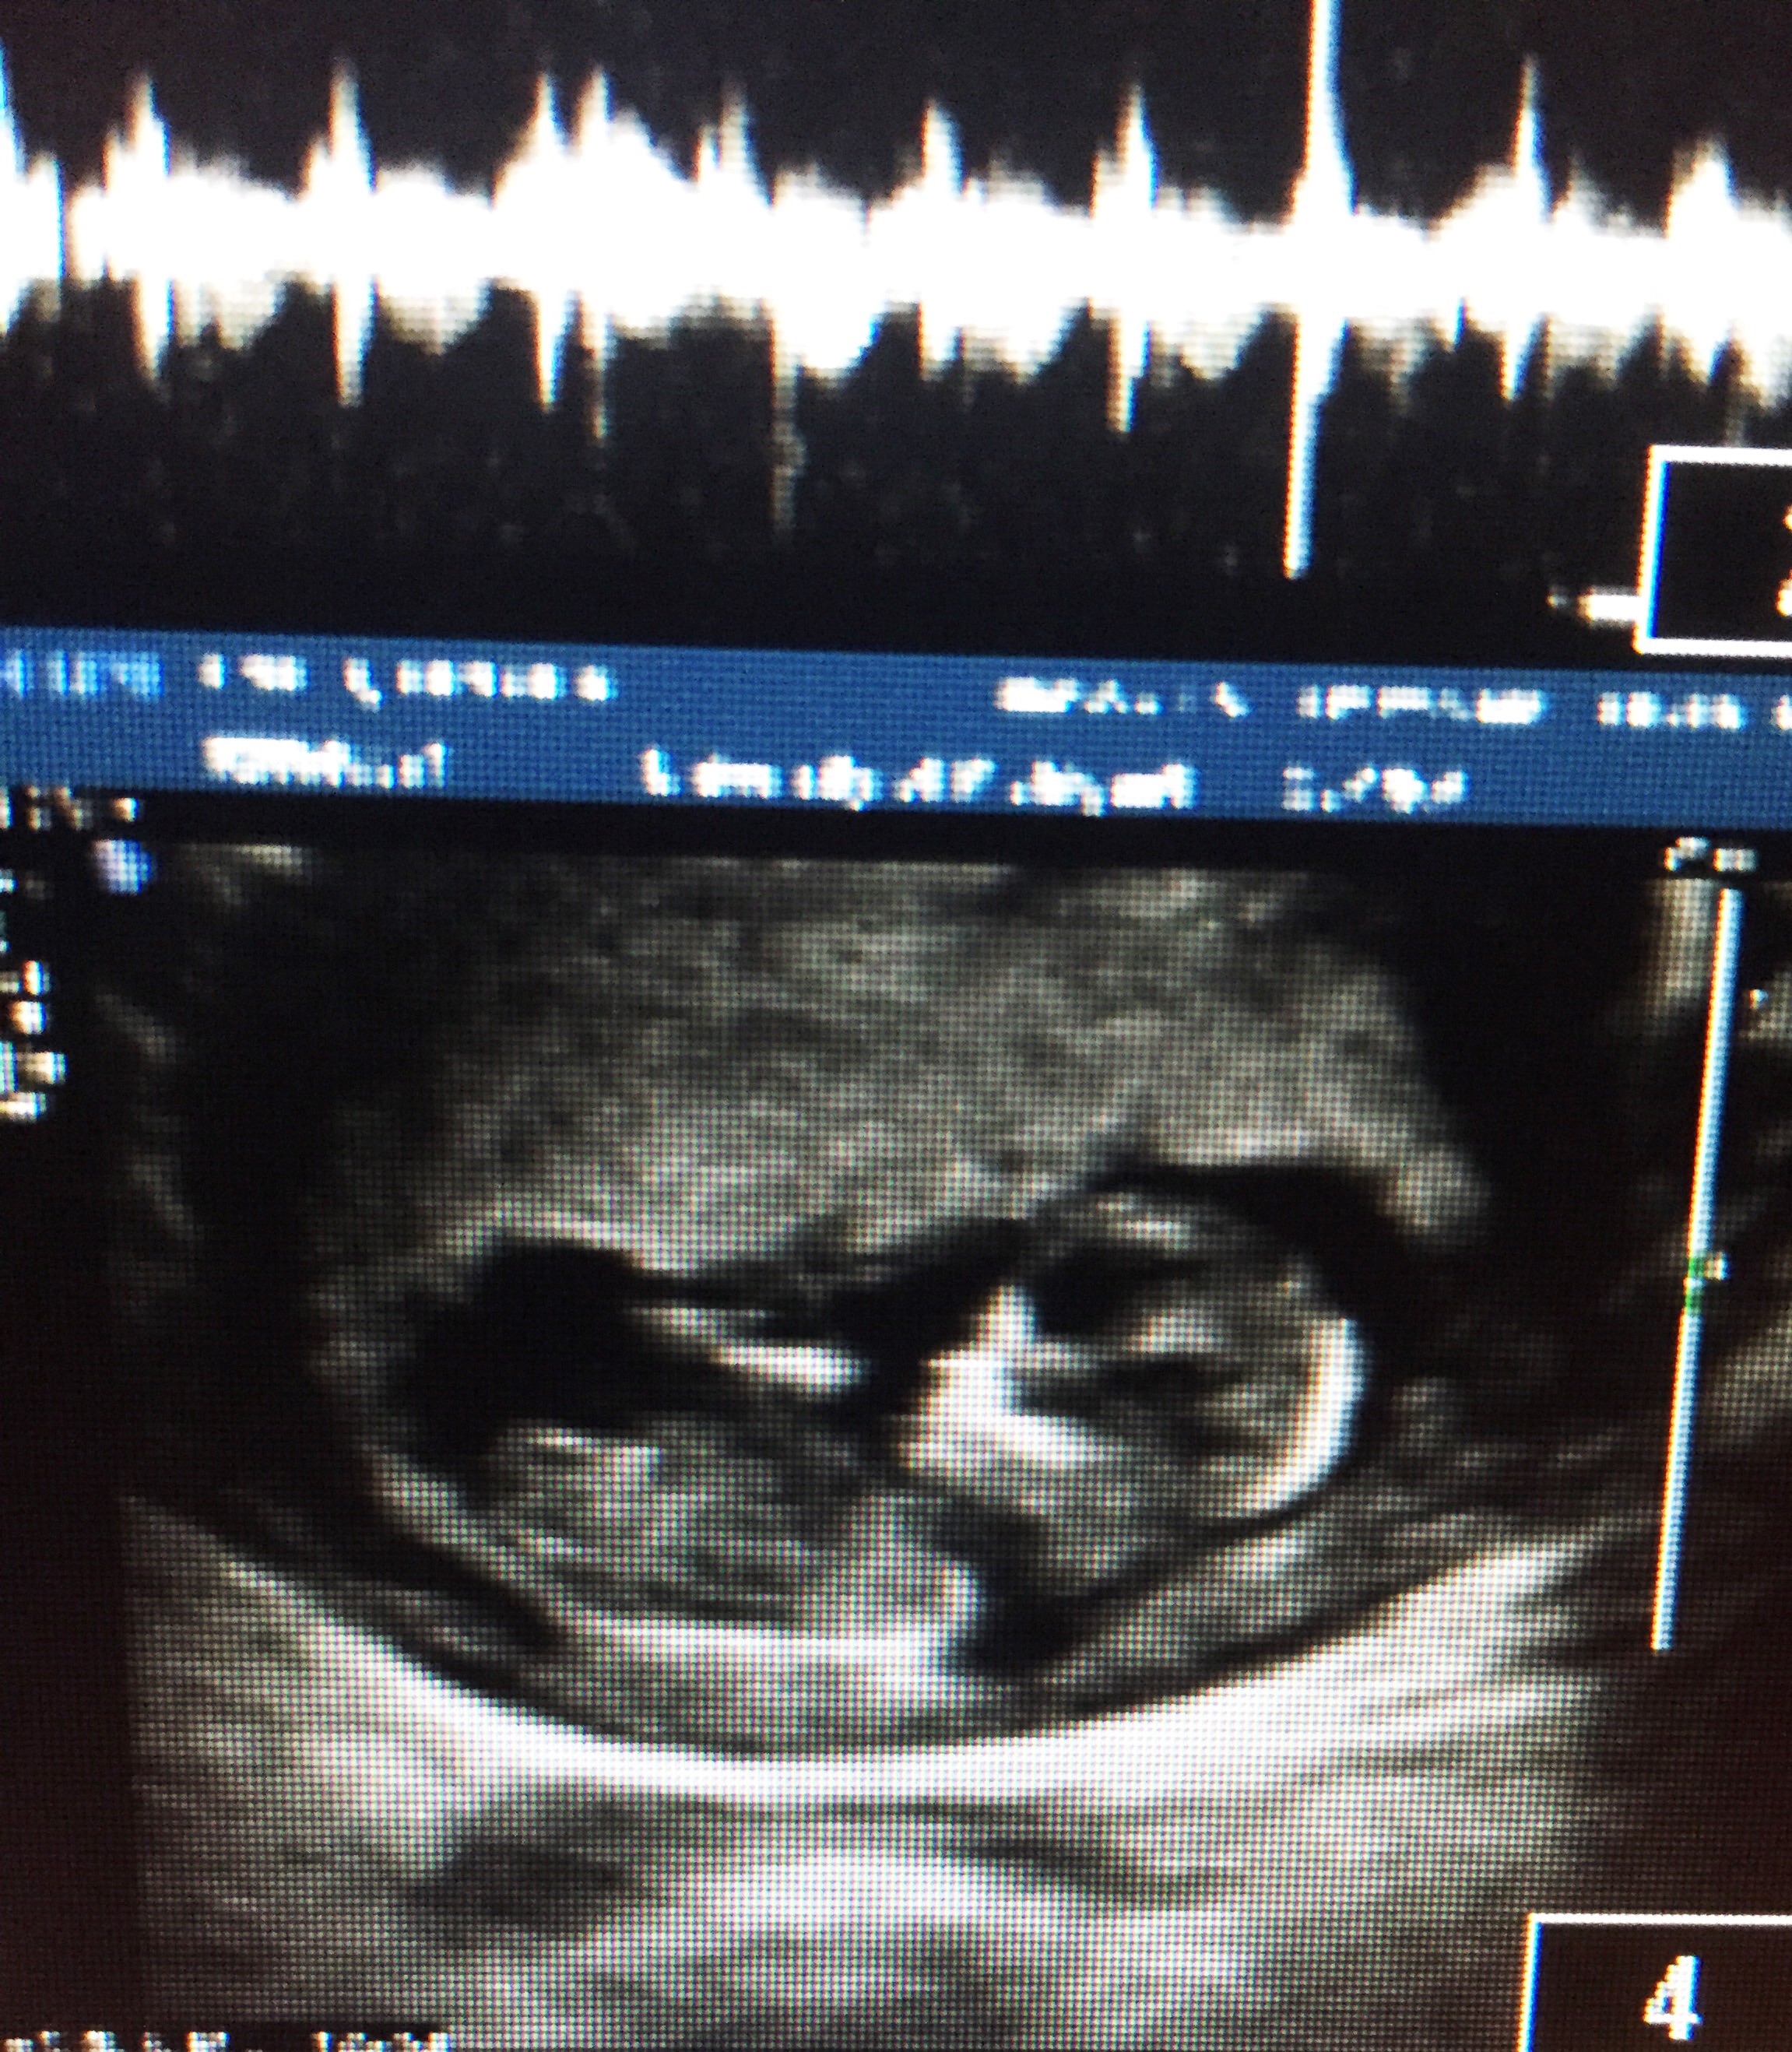

Attachment 25811 A less clear Sagittal pic

Guessing girl. if so congrats on the little sister for your older daughter :)

Yeah looks pretty flat, girl

Girly

Girl.

Girly!

Girl